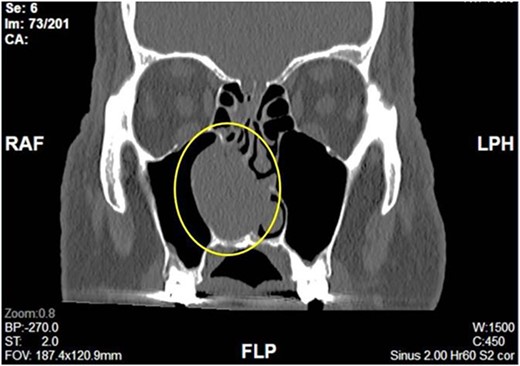

Complete head and neck examination, including flexible nasal endoscopy, revealed a nasal mass emanating from the right maxillary sinus. There was no active bleeding or purulence on his physical exam. The physical exam of the contralateral side was unremarkable. CT scan of the sinuses with IV contrast revealed an expansile soft tissue mass measuring 4.1 × 2.4 × 3.3 cm. The mass involved the middle turbinate and expanded to the medial wall of the maxillary sinus, blocking the right osteomeatal complex. There was evidence of mucosal thickening of the right ethmoid, right frontal, and right maxillary sinus as well as right septal deviation (Figs 1 and 2). Differential diagnosis based on the physical exam and imaging included inverting papilloma, polypoid mass, vascular lesion, malignant neoplasm, and even an infectious process. The patient was scheduled for functional endoscopic sinus surgery with excision of right nasal cavity mass, right frontal, and maxillary sinuplasty as well as ethmoidectomy and possible septoplasty at the ambulatory surgery center.